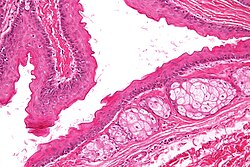

Subdivided into layers:

- Papillary dermis.

- Location: superficial - opposed to the deep aspect of the epidermis.

- Appearance: dense, thick collagen bundles.

- Reticular dermis.

- Location: deep - between papillary dermis and subdermis.

- Appearance: loose connective tissue.